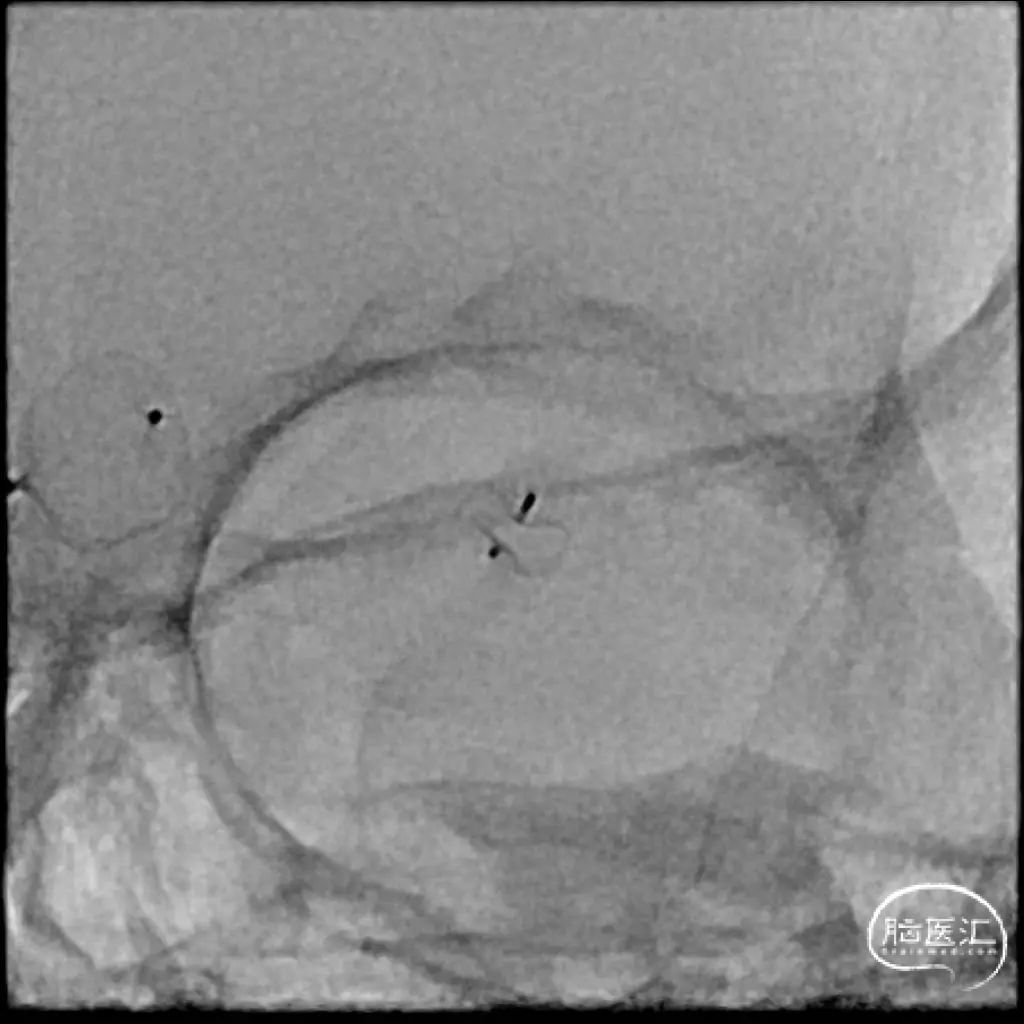

右侧后交通段动脉瘤,大小约13.36mm*13.26mm,瘤体上有子囊形成,床突段至后交通段血管稍狭窄,脉络膜前动脉距瘤颈部有一定距离。

Headway 17微导管塑形后置入动脉瘤瘤体内,半释放18mm*44cm complex弹簧圈成篮,半释放3.5mm*20mm LVIS支架保护瘤颈后完全释放18mm*44cm complex弹簧圈成篮,后依次释放6枚弹簧圈栓塞动脉瘤,最后一枚弹簧圈释放完成后造影,后交通动脉瘤少量造影剂进入,完全释放支架,右侧后交通动脉瘤瘤体内极少量造影剂进入,子囊不显影,Raymond分级3级,同时造影见各主干级分支血管显影良好,遂退出系统。

手术顺利,麻醉满意,术中生命体征平稳。